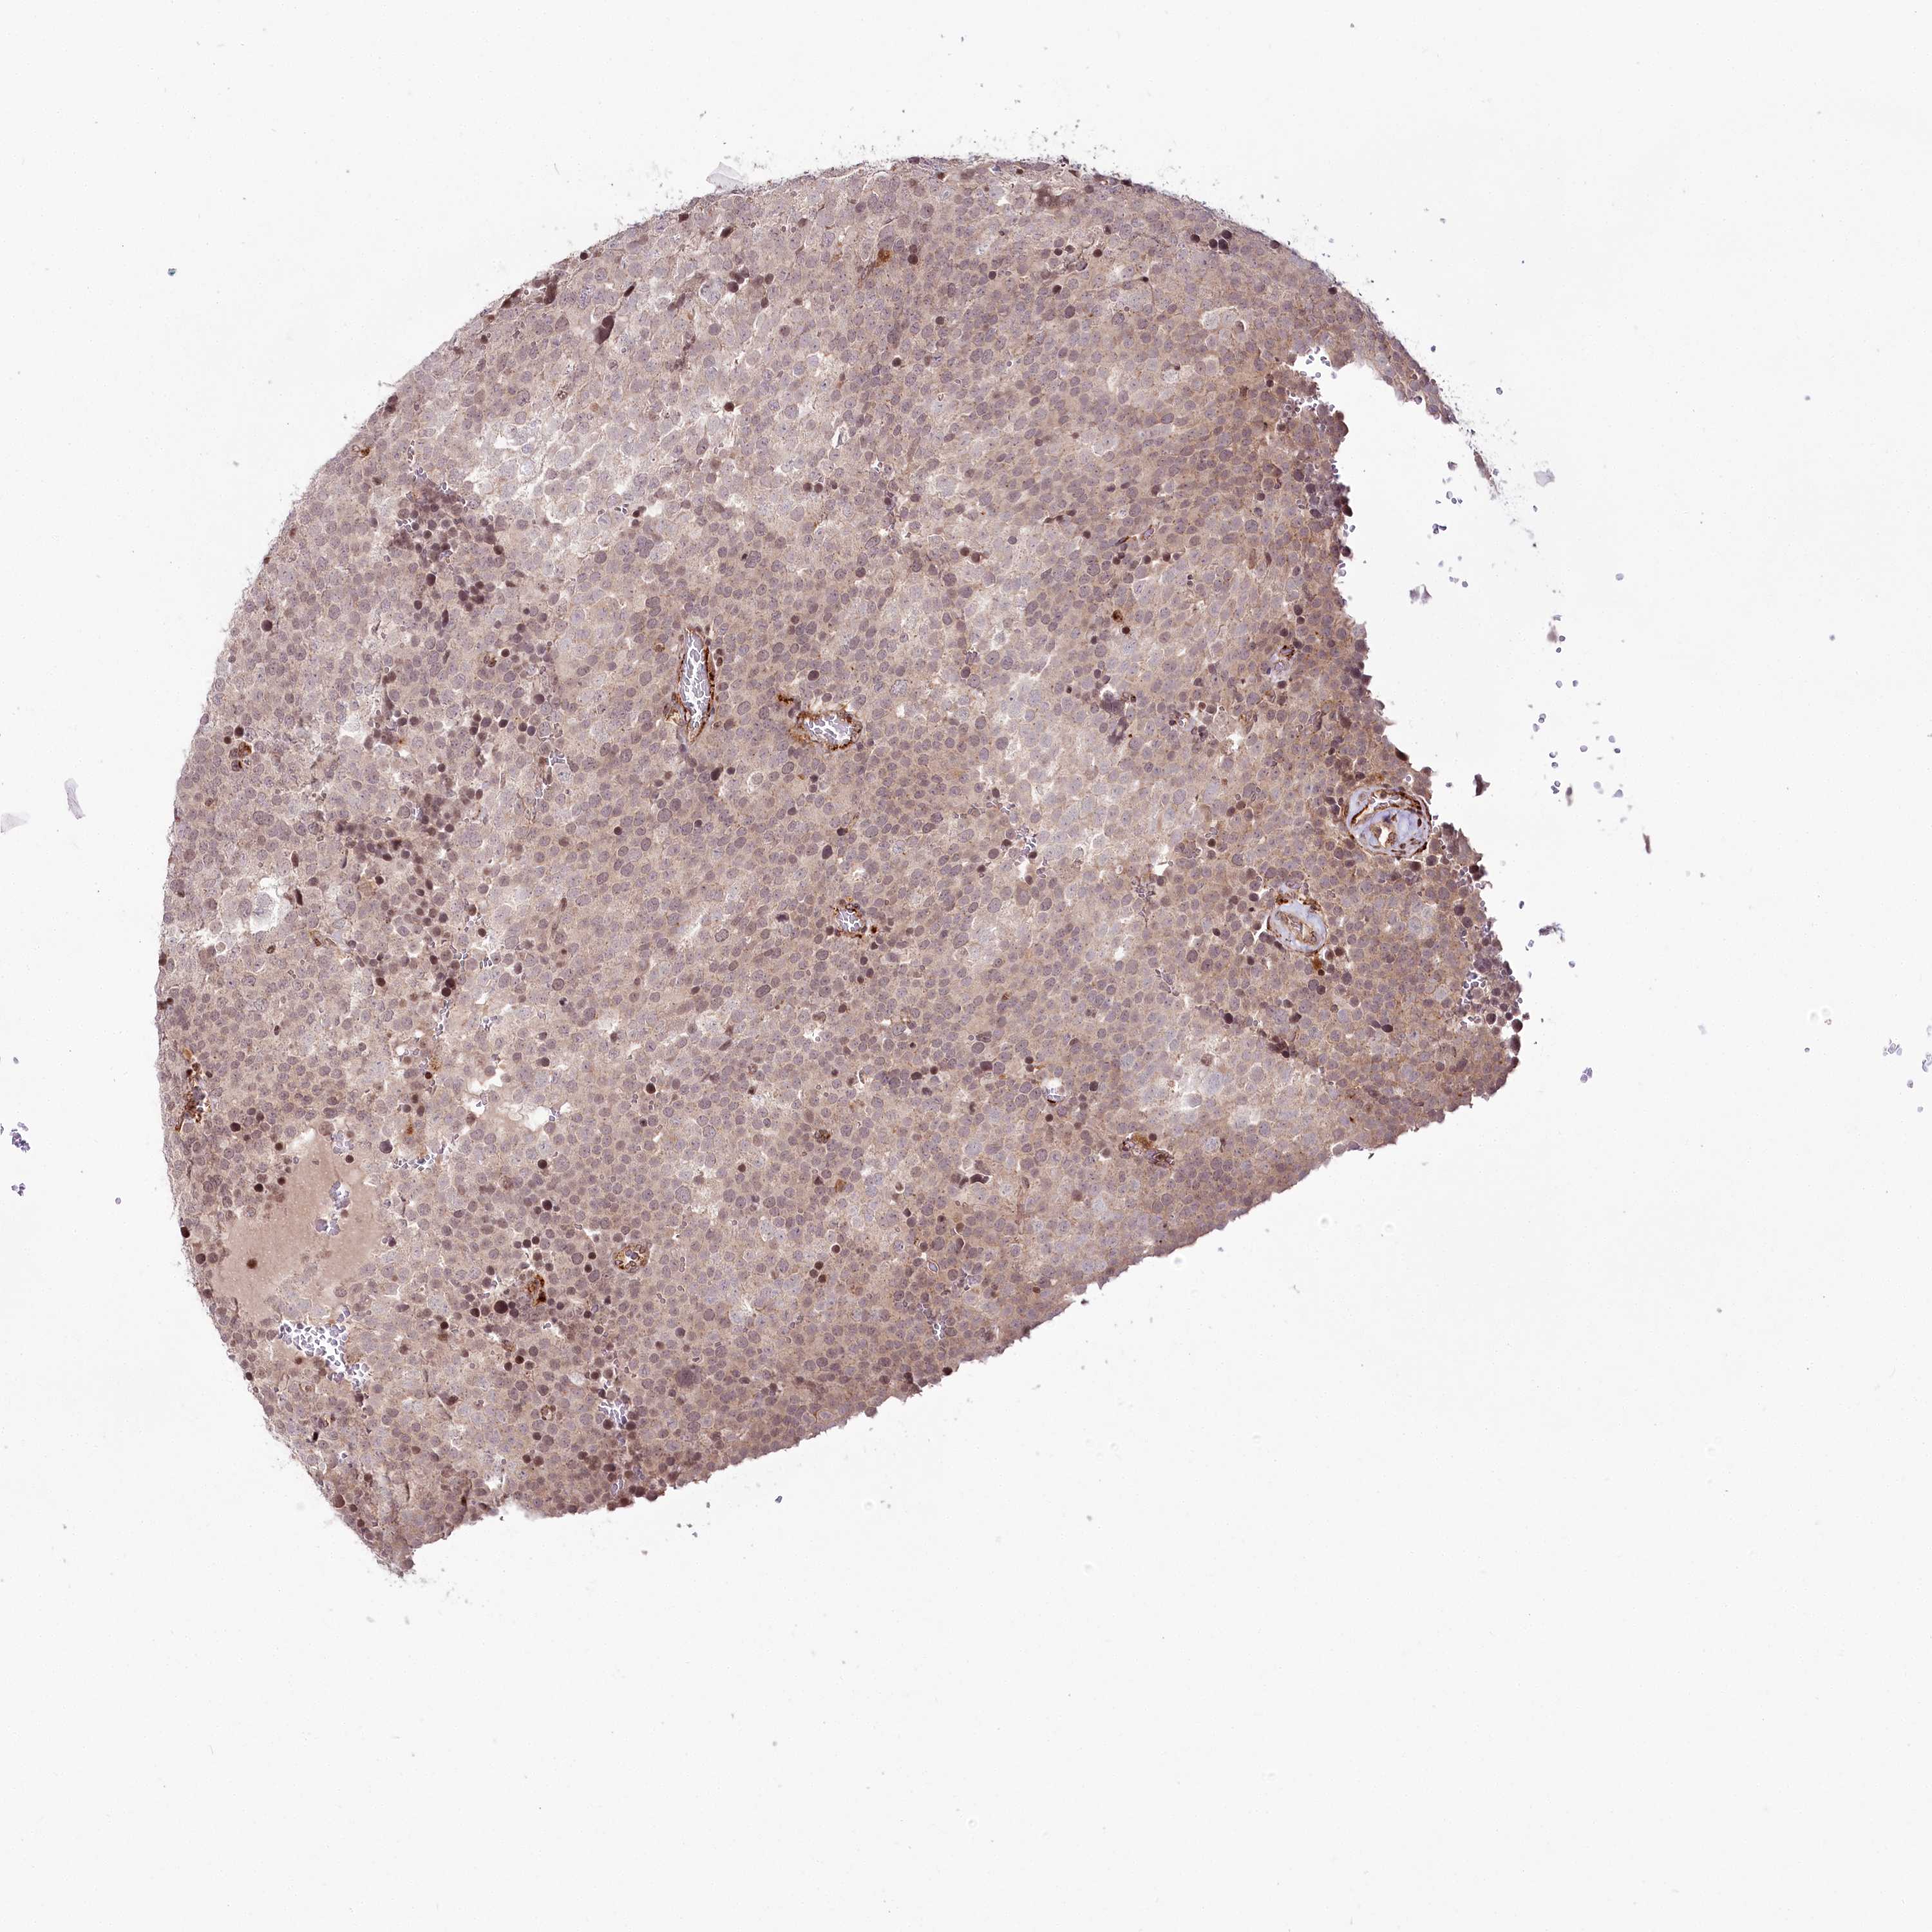

TESTIS CANCER - Protein expressioni

A mouse-over function shows sample information and annotation data. Click on an image to view it in a full screen mode. Samples can be filtered based on level of antibody staining by selecting one or several of the following categories: high, medium, low and not detected. The assay and annotation is described here.

Note that samples used for immunohistochemistry by the Human Protein Atlas do not correspond to samples in the TCGA dataset.

Antibody stainingi

Antibody staining in the annotated cell types in the current human tissue is reported as not detected, low, medium, or high, based on conventional immunohistochemistry profiling in selected tissues. This score is based on the combination of the staining intensity and fraction of stained cells.

Each image is clickable and will lead to virtual microscopy that enables deeper exploration of all samples and also displays staining intensity scores, fraction scores and subcellular localization as well as patient and tissue information for each sample.

Antibody HPA028911

Antibody CAB037020

Staining

High

Medium

Low

Not detected

Intensity

Strong

Moderate

Weak

Negative

Quantity

>75%

75%-25%

<25%

None

Location

Nuclear

Cytoplasmic/membranous

Cytoplasmic/membranous,nuclear

Carcinoma, Embryonal, NOS

Seminoma, NOS